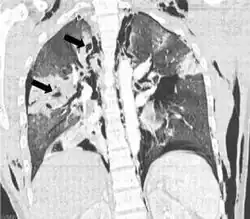

| Coronal CT scan showing lucencies (pale areas in radiography) in the lung caused by pulmonary lacerations on the left of the image (black arrows) | |

Pulmonary laceration may not be visible using chest X-ray because an associated pulmonary contusion or hemorrhage may mask it.[1][9] As the lung contusion clears (usually within two to four days), lacerations begin to become visible on chest X-ray.[3] CT scanning is more sensitive and better at detecting pulmonary laceration than X-rays are,[1][5][12][15] and often reveals multiple lacerations in cases where chest X-ray showed only a contusion.[12] Before CT scanning was widely available, pulmonary laceration was considered unusual because it was not common to find with X-ray alone.[12] On a CT scan, pulmonary lacerations show up in a contused area of the lung,[9] typically appearing as cavities filled with air or fluid[16] that usually have a round or ovoid shape due to the lung's elasticity.[4]

Hematomas appear on chest radiographs as smooth masses that are round or ovoid in shape.[1] Like lacerations, hematomas may initially be hidden on X-ray by lung contusions, but they become more apparent as the contusion begins to heal.[1] Pneumatoceles have a similar shape to that of hematomas but have thin, smooth walls.[17] Lacerations may be filled completely with blood, completely with air, or partially with both.[4] Lacerations filled with both blood and air display a distinctive air-fluid level.[4] A single laceration may occur by itself, or many may be present, creating an appearance like Swiss cheese in the radiography of the lung.[4]